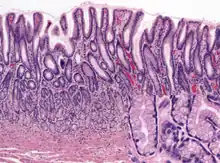

Microanatomy

Wall

Like the other parts of the gastrointestinal tract, the human stomach walls consist of a mucosa, submucosa, muscularis externa, subserosa and serosa.[16]

The inner part of the lining of the stomach, the gastric mucosa, consists of an outer layer of column-shaped cells, a lamina propria, and a thin layer of smooth muscle called the muscularis mucosa. Beneath the mucosa lies the submucosa, consisting of fibrous connective tissue.[17] Meissner's plexus is in this layer interior to the oblique muscle layer.[18]

Outside of the submucosa lies another muscular layer, the muscularis externa. It consists of three layers of muscular fibres, with fibres lying at angles to each other. These are the inner oblique, middle circular, and outer longitudinal layers. The presence of the inner oblique layer is distinct from other parts of the gastrointestinal tract, which do not possess this layer.[19] Stomach contains the thickest muscularis layer consisting of three layers, thus maximum peristalsis occurs here.

Glands

The mucosa lining the stomach is lined with a number of these pits, which receive gastric juice, secreted by between 2 and 7 gastric glands. Gastric juice is an acidic fluid containing hydrochloric acid and the digestive enzyme pepsin. The glands contains a number of cells, with the function of the glands changing depending on their position within the stomach.

Within the body and fundus of the stomach lie the fundic glands. In general, these glands are lined by column-shaped cells that secrete a protective layer of mucus and bicarbonate. Additional cells present include parietal cells that secrete hydrochloric acid and intrinsic factor, chief cells that secrete pepsinogen (this is a precursor to pepsin- the highly acidic environment converts the pepsinogen to pepsin), and neuroendocrine cells that secrete serotonin.[20]

Glands differ where the stomach meets the esophagus and near the pylorus.[21] Near the junction between the stomach and the esophagus lie cardiac glands, which primarily secrete mucus.[20] They are fewer in number than the other gastric glands and are more shallowly positioned in the mucosa. There are two kinds - either simple tubular with short ducts or compound racemose resembling the duodenal Brunner's glands. Near the pylorus lie pyloric glands located in the antrum of the pylorus. They secrete mucus, as well as gastrin produced by their G cells.[22]